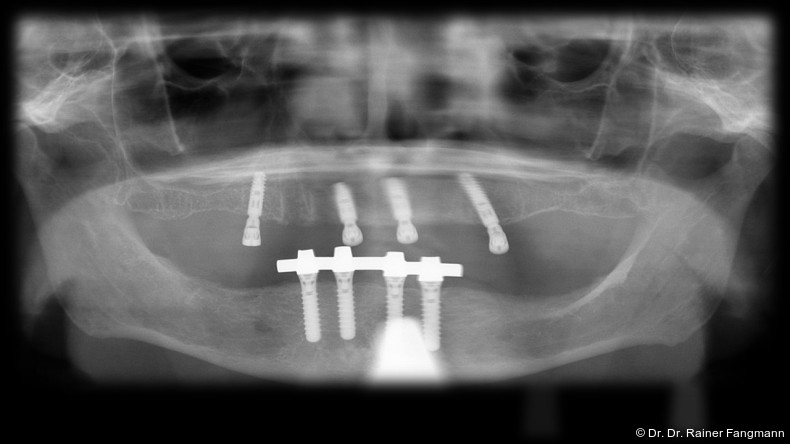

Die Fragestellung zur Implantatanzahl im Oberkiefer oder Unterkiefer ist oft sehr patienten- und behandlerspezifisch zu betrach-ten. Für Kostenträger ist die Frage oft von übergeordneter Relevanz. Für den Praktiker stellt sich die Frage nach der Umsetzbarkeit. Zudem sind auch das Knochenangebot und dessen Qualität für die Anzahl der Implantate und auch der Implantattypus maßgebend. Folgender Beitrag zeigt ein Fallbeispiel mit drei Implantaten, sechs Jahre in situ.

Ein immer viel diskutiertes Thema ist die Implantatanzahl beim All-on-X-Konzept. Diese ist von vielen Faktoren abhängig. Zu nennen sind der Implantattyp, der Implantatdurchmesser und die Implantatinnengeometrie. Im Weiteren sind die Knochenqualität und -quantität zu betrachten. Auch spielt die Gegenbezahnung zum All-on-X-Kiefer eine entscheidende Rolle, sodass hier keine einheitliche Linie für den Oberkiefer erkennbar ist. Es gelten in der Regel vier bis sechs Implantate als ausreichend. Im Unterkiefer sind es in der Regel vier. Wie dargestellt, reichen bei diesem Implantatsystem auch drei Implantate aus.